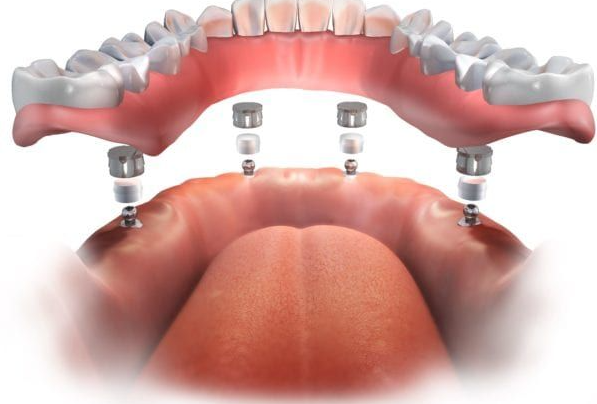

01. 임플란트 틀니

오버덴처 임플란트라고도 하는 임플란트 틀니는 위턱 혹은 아래턱에 각각 2~4개의 임플란트를 식립한 후 틀니를 탈착하는 방식입니다.

탈착이 가능하기에 관리가 쉬우며, 임플란트로 고정을 하기 때문에 일반적인 틀니에 비해 높은 저작력과 사용감을 느끼실 수 있습니다.

물론 기존의 틀니보다는 비쌀 수 있지만, 임플란트보다는 저렴하기 때문에 비용적으로도 합리적이다 볼 수 있겠습니다.